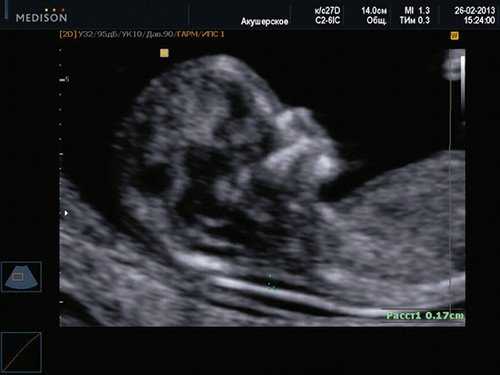

Диагноз хориальности и количества амнионов

УЗИ при двойне в основном должно выявить хориальность (ди- или монохориальность) и для монохориальных беременностей (моно- или диамниотических) - количество амнионов. При многоплодной беременности эта информация необходима для соответствующего ведения дискордантной мальформации, замедления роста, внутриутробной гибели плода или получения образцов ткани плода. Точность этой диагностики в течение I триместра может достигать 100%, а затем на протяжении беременности она уменьшается [7]. Дихориальность подтверждают выявлением лямбда-признака (рис. 4a). Наоборот, монохориальность диагностируют при отсутствии визуализации лямбда-признака или выявлении T-признака (рис. 4b) в межамниотической мембране, расположенной перпендикулярно хорионической пластине.

Рис. 4. Диагностика хориальности и количества амнионов в I триместре путем оценки лямбда-признака (a) и T-признака (b).